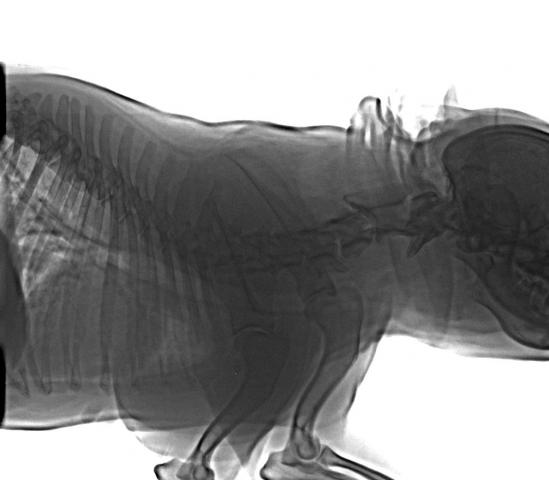

Французский бульдог,6 лет.Стала плохо ходить,что- то с позвоночником.Врачи не могут поставить диагноз.Есть снимки.Помогите!

Снимки хорошие, качественные, но совершенно не информативные. На этих пленках патология не определяется. Но здесь нет снимка, который нужен обязательно - поясничный отдел позвоночника в прямой проекции (такой, как 3-й, но только не шея, а поясница).

Нет,наоборот.Собака сначала стала немного наклонять голову вправо.Когда были на консультации у окулиста,то он обратил внимание на это ,сказал,что есть какие-то изменения в области шеи.Я отсутствовала дома 2 недели.Приехала,собаку вообще не узнала.Крен головы вправо стал еще сильнее,передние ноги как-то ослабли.Она идет,может споткнуться,упасть.Сходили,сделали рентген.снимок.Поставили диагноз:атланто-аксиальная нестабильность шейного отдела,спондилоартроз. Проколола 5 дней:актовегин,папаверин,комбилипн,мидокалм,дексаметазон. Пока делала уколы и еще дней 5 после этого собаке стало легче,а потом опять вернулись к тому, что было.На консультации врач сказал,что дальше просто колоть преднизалон. Я уехала к другому врачу,тот сделал снимки,которые я Вам отослала.Сказал, что диагноз не подтверждает,на пальцах показал, что со спинным мозгом все нормально.С помощью какой-то процедуры (бумаги на работе)обнаружил перфорацию барабанной перепонки.Выписал лечение:цефтриаксон,циклоферон,цебролизин(колола 2 дня,стало хуже),комбилипен.В уши-изотик.Сказал,что может быть у собаки был инсульт.Собаке от лечения хуже.Вот такие дела.